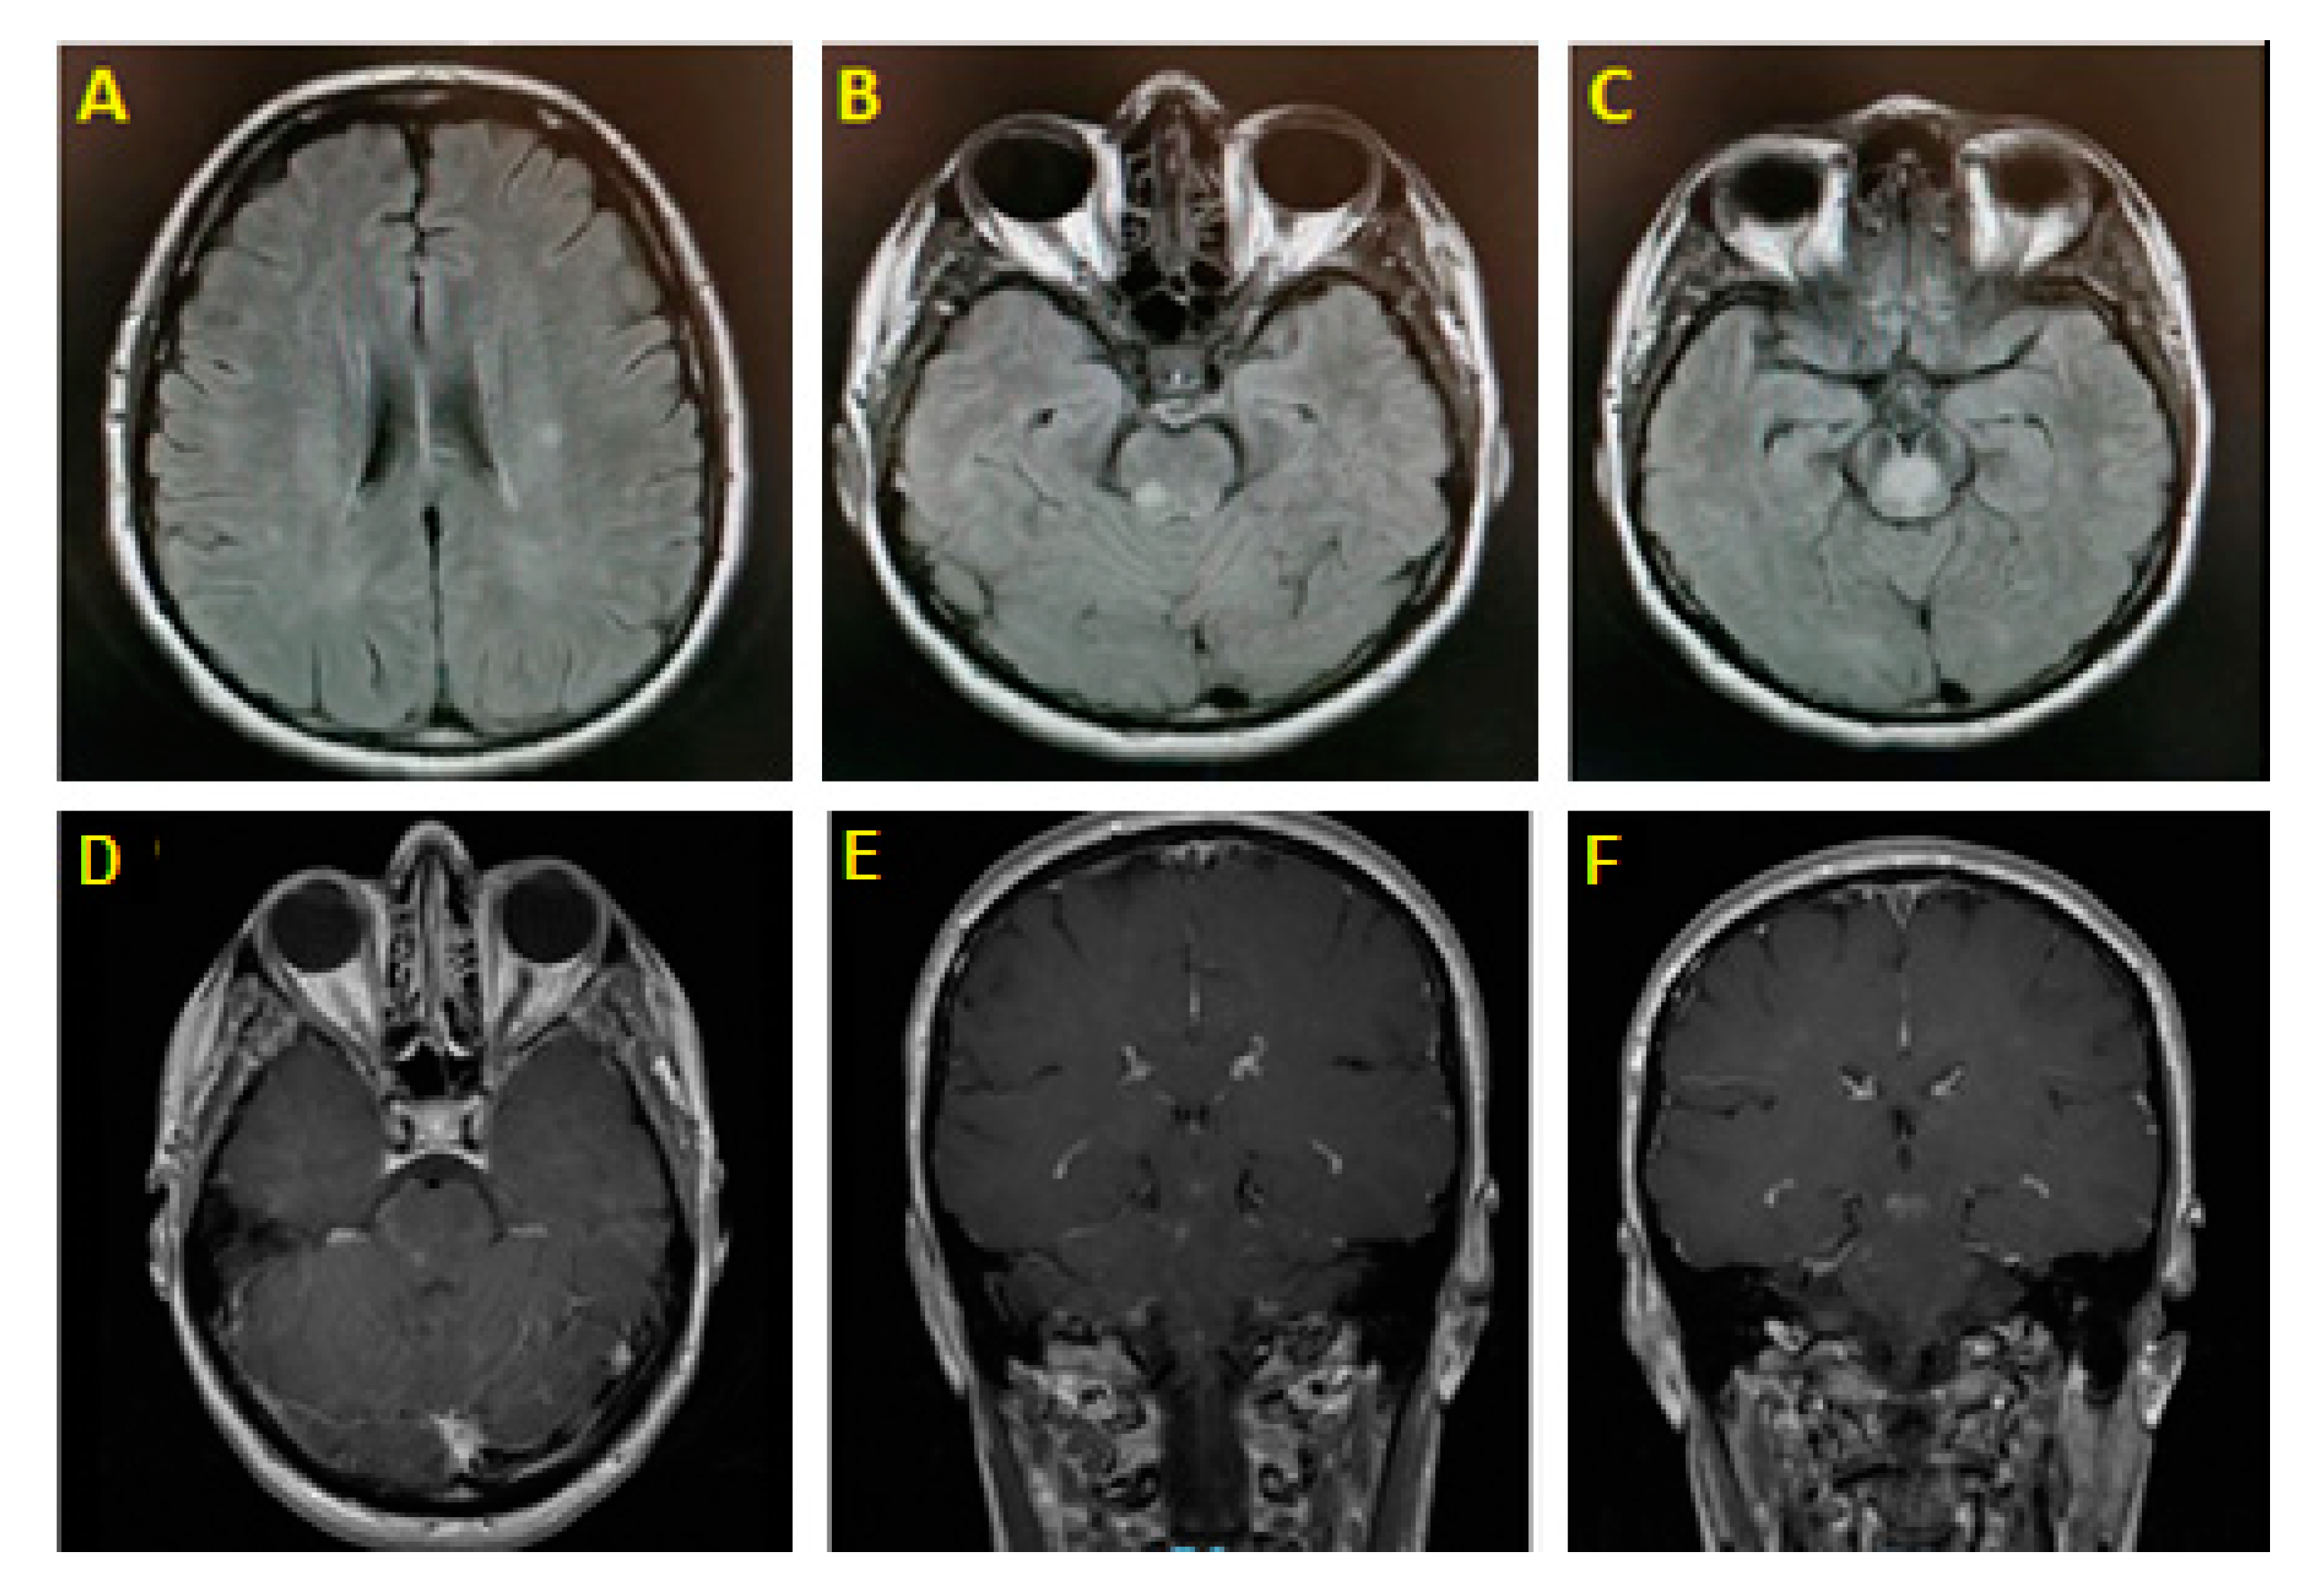

Brain magnetic resonance imaging (MRI) with gadolinium showed an enhancing midbrain lesion and multiple high T2/FLAIR punctate nonenhancing subcortical white matter (WM) lesions (Figure 1). Magnetic resonance angiography of the head and neck was unrevealing. Basic metabolic panel and cerebrospinal fluid (CSF) studies (including testing for IgG index and oligoclonal bands) were unremarkable. Whole-body CT-scan was unremarkable. Visual evoked potential showed no evidence of optic neuritis. Serum anti-aquaporin-4 antibodies were negative; however, antimyelin oligodendrocyte glycoprotein (anti-MOG) antibodies returned positive (1:40).

Figure 1. (A): Axial T2/FLAIR shows bilateral foci signal hyperintensities in the subcortical white matter. (B): Right pontine T2/FLAIR hyperintensity. (C): Midbrain hyperintense signal. (DF): Subcortical lesions showing postcontrast enhancement.